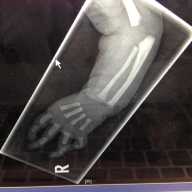

The boy underwent a three-hour correctional procedure at Cohen Children’s Medical Center on April 27 where his right index finger was shortened, rotated, and moved into the place of the thumb. A metal pin will hold the finger in place so a pseudo joint can form from the bone.

According to Dr. Nick Bastidas, the pediatric plastic surgeon who treated Brandon, patients with Duane-radial ray syndrome are too rare to statistically quantify, with only about 30 cases reported around the globe. Although the young boy will still only have four fingers and a 30 to 40 percent weakness in his new thumb, he will be able to hold and grasp objects normally after undergoing some physical therapy to perfect his use of the new digit.